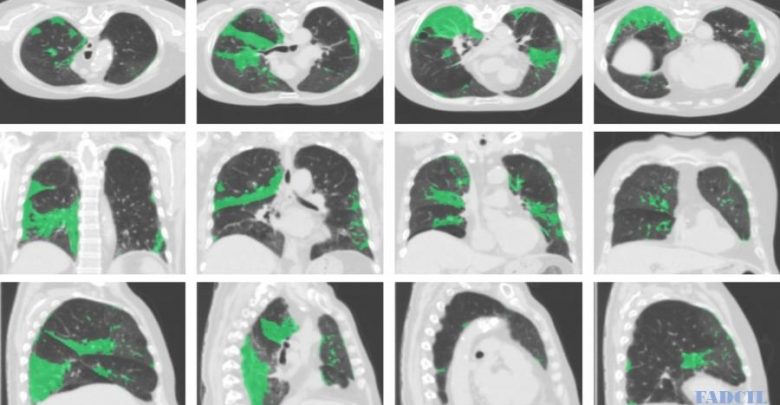

Estudo produzido por 8 cientistas brasileiros apontou que o novo coronavírus é capaz de invadir o cérebro. A pesquisa foi realizada por acadêmicos ligados à UFRJ (Universidade Federal do Rio de Janeiro), Fiocruz (Fundação Oswaldo Cruz) e o Instituto D’Or. O trabalho foi pré-publicado na plataforma internacional bioRxiv nessa 2ª feira (14.set.2020) com o título “Infecção … Continue lendo Estudo de cientistas brasileiros aponta que coronavírus pode invadir o cérebro